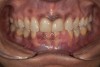

Fig 1. Preoperative frontal smile view.

Figure 1

A 40-year-old female patient complained of short teeth and asked for various options to improve her smile. On clinical examination, the palatal surfaces of the maxillary anterior teeth were found to be eroded, with the residual tooth structure having a smooth and shiny appearance (Figure 1 through Figure 3). In MIP, no restorative space was available, as the lower anterior teeth fit tightly into the upper palatal surfaces, making this a clinically challenging situation to treat conservatively. In most cases of conventional treatment protocols, such upper teeth are devitalized and restored with crowns that structurally leave the teeth in a compromised condition.10